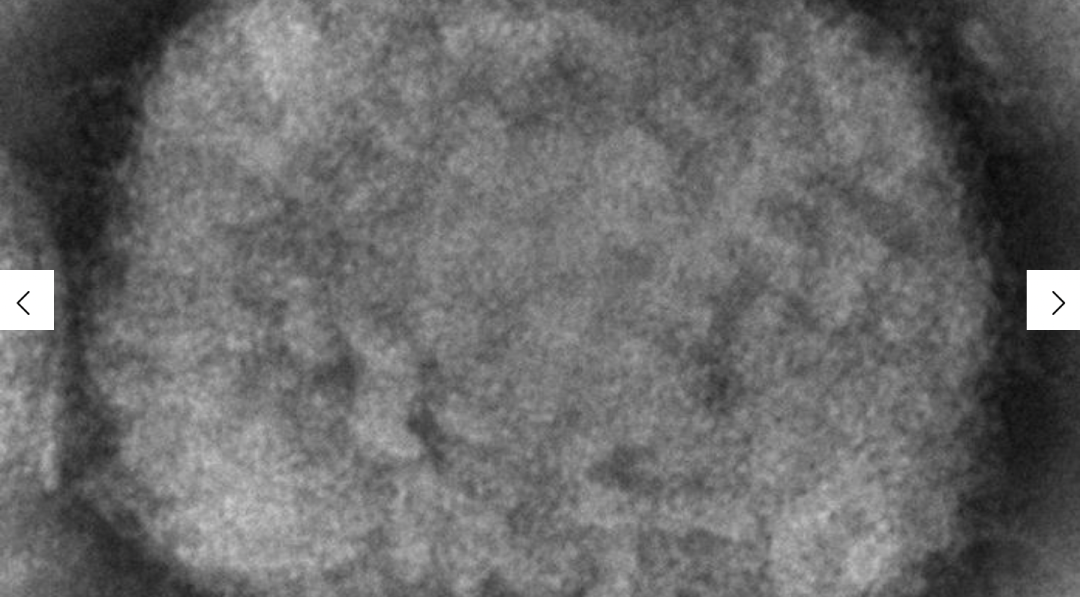

猴痘于 1958 年被发现;它是一种由与引起天花的病毒属于同一家族的病毒引起的罕见疾病。